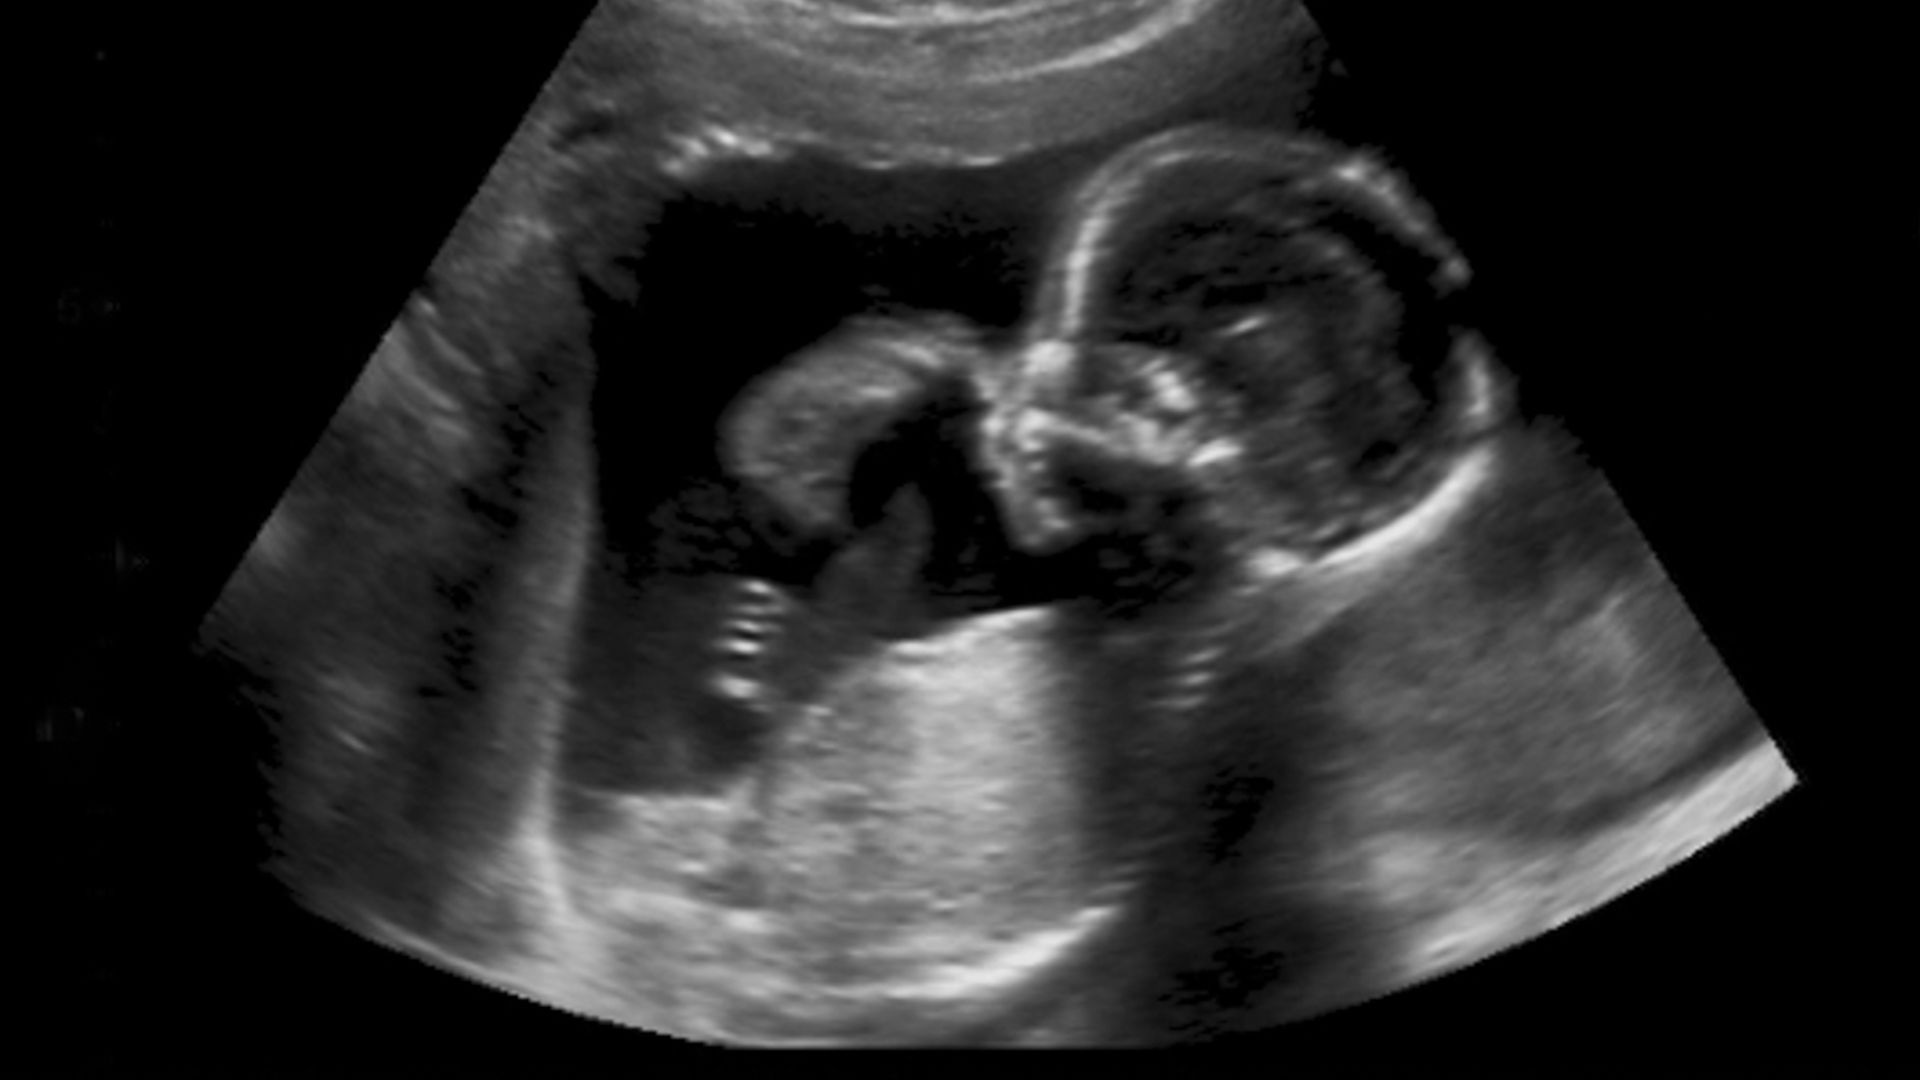

Ultraschalluntersuchungen laut Mutter-Kind-Pass

Der Mutter-Kind-Pass sieht drei Ultraschalluntersuchungen vor: Die erste dient der Bewertung der frühen Entwicklung des Kindes, die zweite überprüft Herzaktion, Fruchtwassermenge und Plazentasitz, und die dritte untersucht Herzaktion, Wachstum, Plazentasitz, Lage des Kindes und Fruchtwassermenge.